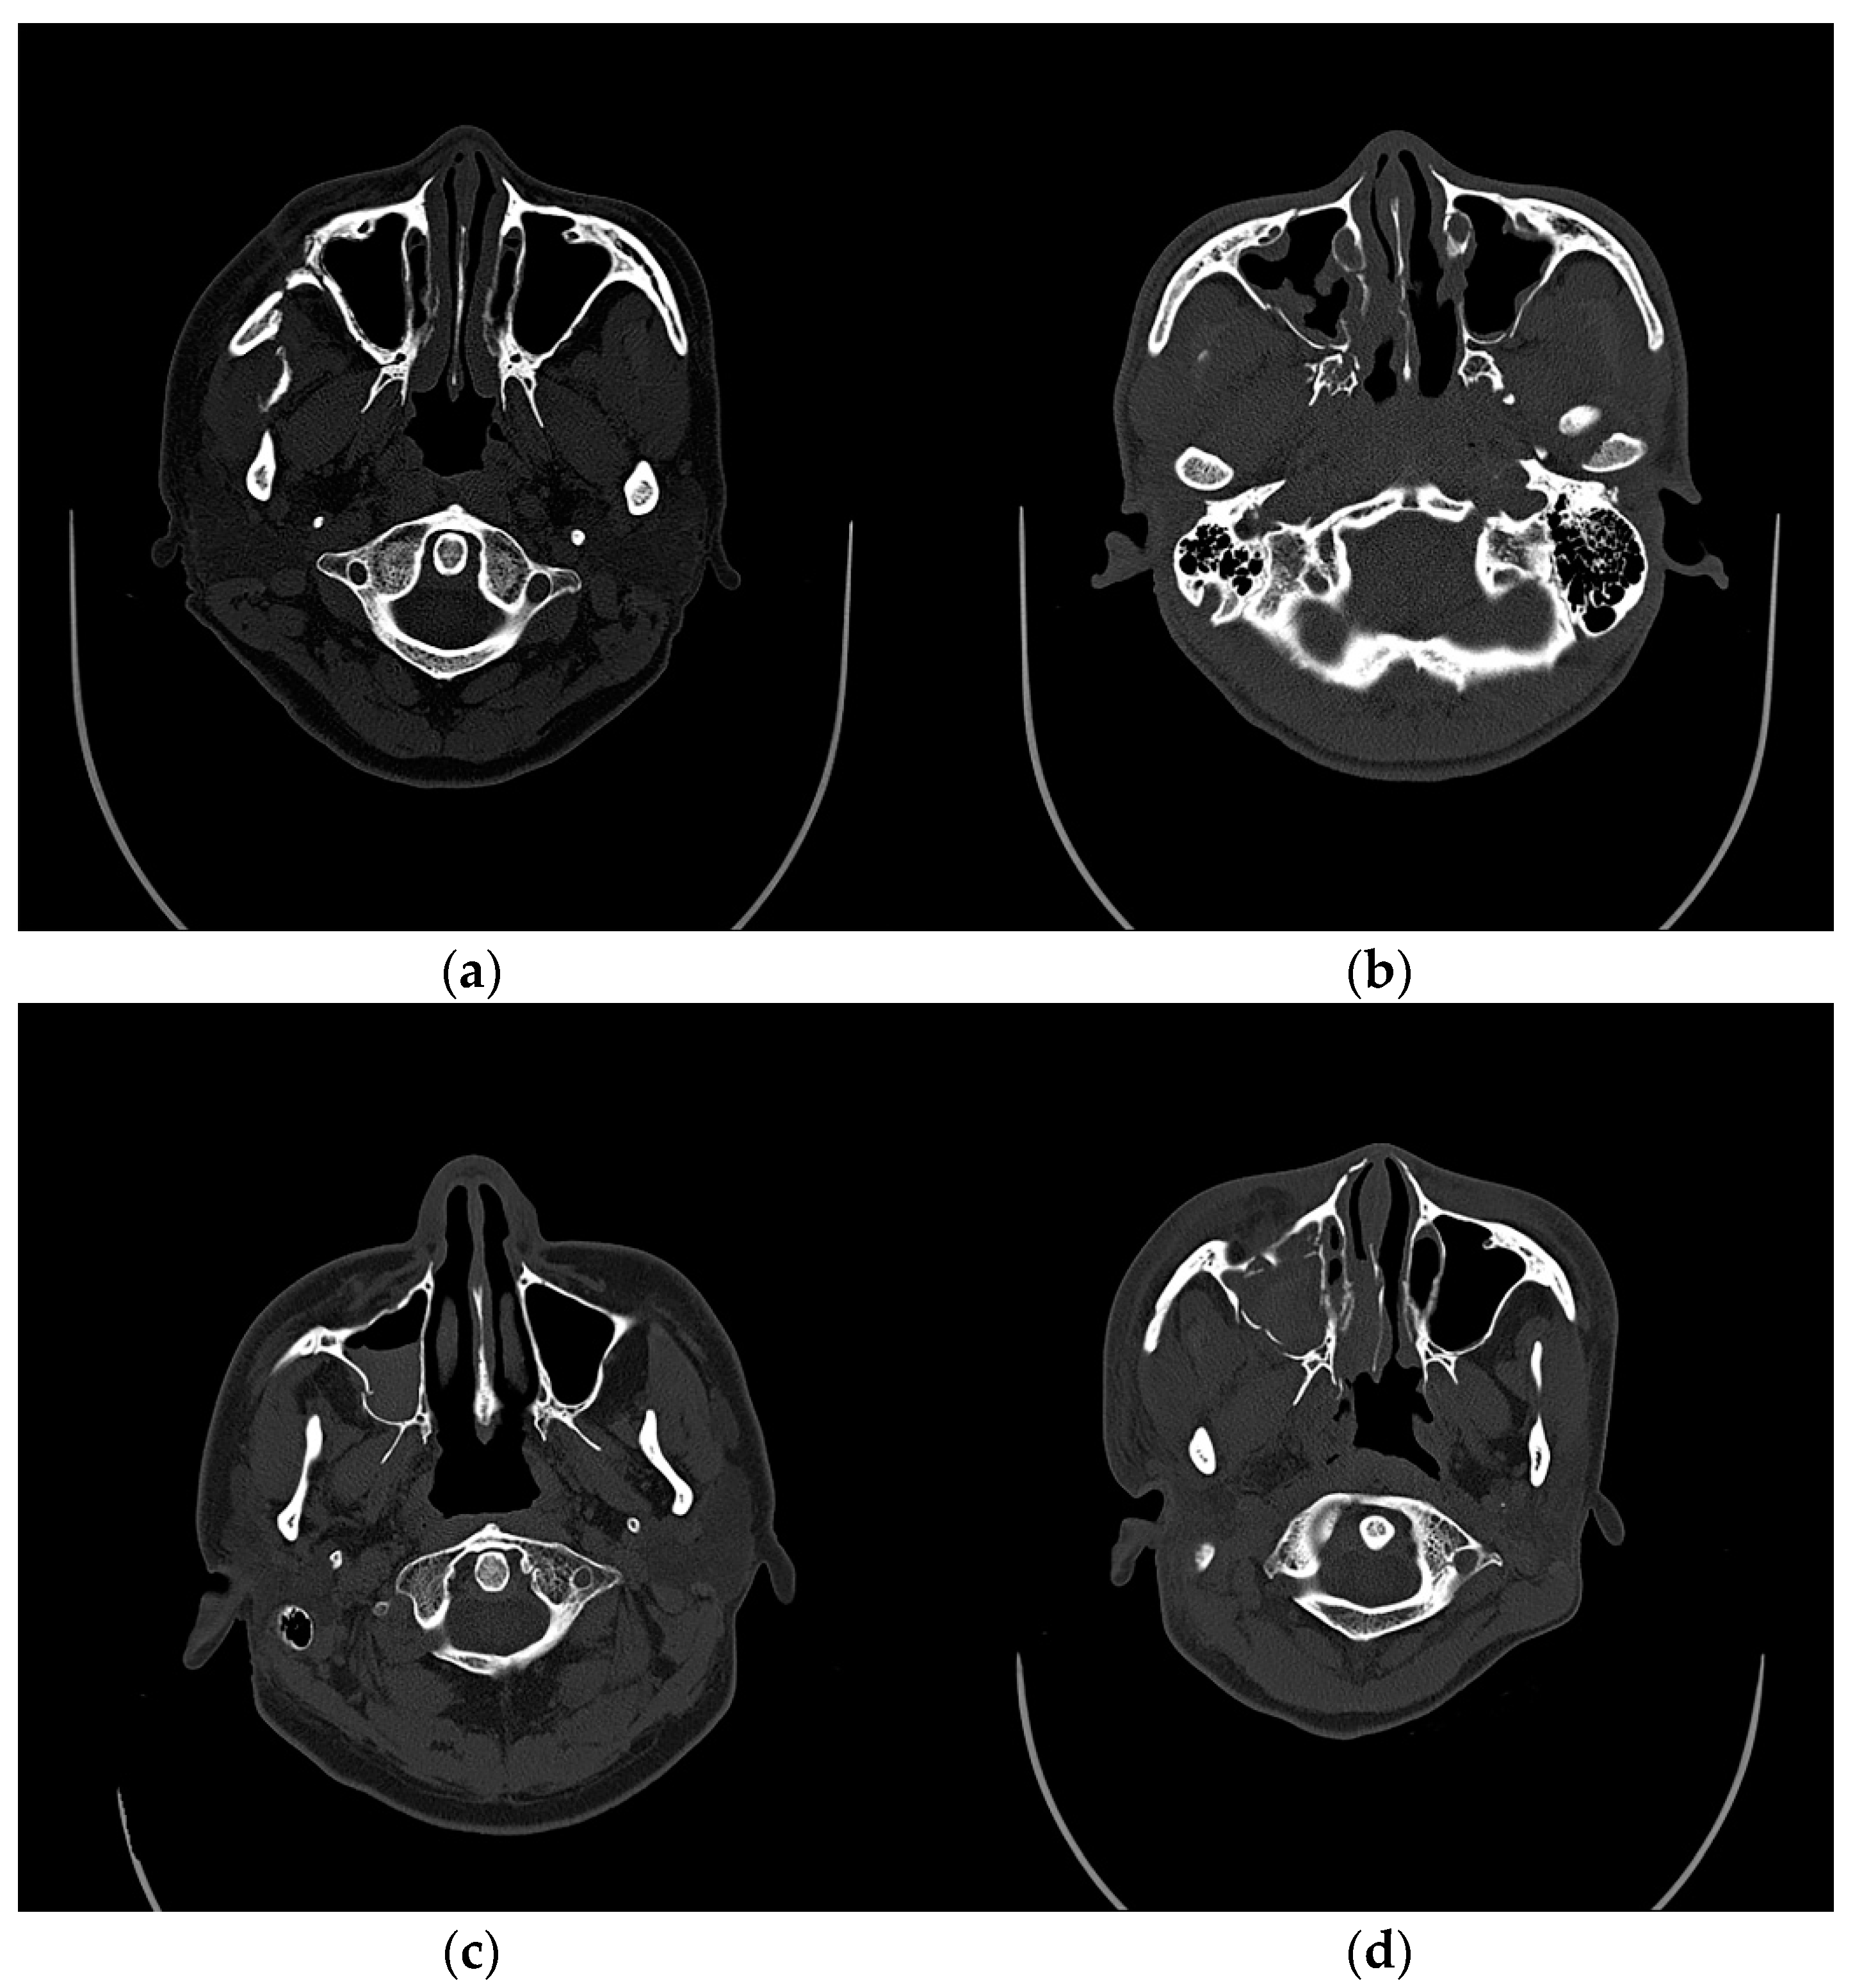

2. Materials and Methods

2.2. Study Population

2.3. Factors of Interest and Data Collection